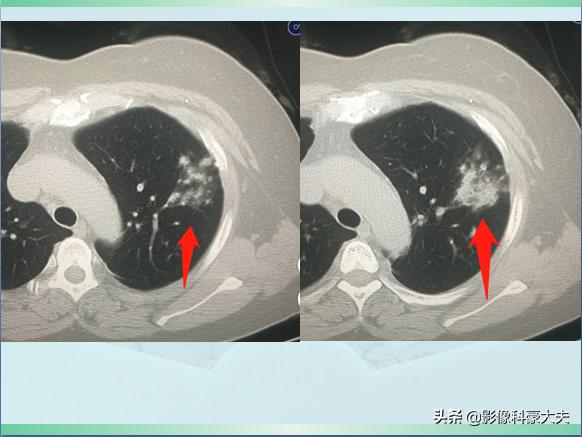

星星点点的小斑片影

上图是一位54岁女病人,因为发烧、咳嗽3天做肺部CT,发现左上肺斑片状影,密度不均,边界不清,提示肺炎。

使用抗生素治疗4天后复查,病灶密度增加,同时内部出现了几个小空洞:

融合实变,可见空洞

空洞通常是肺组织发生坏死、液化,经支气管随痰液排出后形成的,什么细菌这么厉害,会在短短4天发生坏死呢?